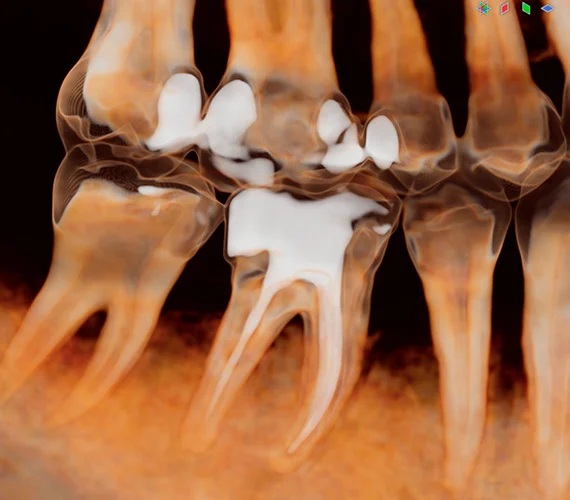

Nástroje pro endodoncii - Všechny naše 3D zobrazovací jednotky disponují speciálním vysokým rozlišením s velikostí voxelu 75 µm, které bylo navrženo přímo pro endodontické snímkování. V kombinaci s vynikajícími vizualizačními možnostmi softwaru Romexis je tento režim ideální pro endodontickou diagnostiku i edukaci pacienta. Lze snadno vyhodnotit kořenové kanálky, úrazy, zlomeniny kořenů i jejich resorpci – což umožňuje přesné stanovení diagnózy a plánování ošetření.

Výkonné diagnostické nástroje ve 3D - Univerzální diagnostické náhledy modulu Romexis 3D poskytují okamžitý přehled o anatomii pacienta – umožňují zobrazit snímky z různých projekcí nebo je automaticky převést na panoramatické snímky a řezy. Měřicí a značicí nástroje softwaru – jako je trasování nervového kanálu – dále podporují bezpečné a přesné plánování ošetření. Různé možnosti 3D zobrazení zlepšují vizualizaci a zároveň slouží jako skvělý nástroj pro edukaci pacientů.